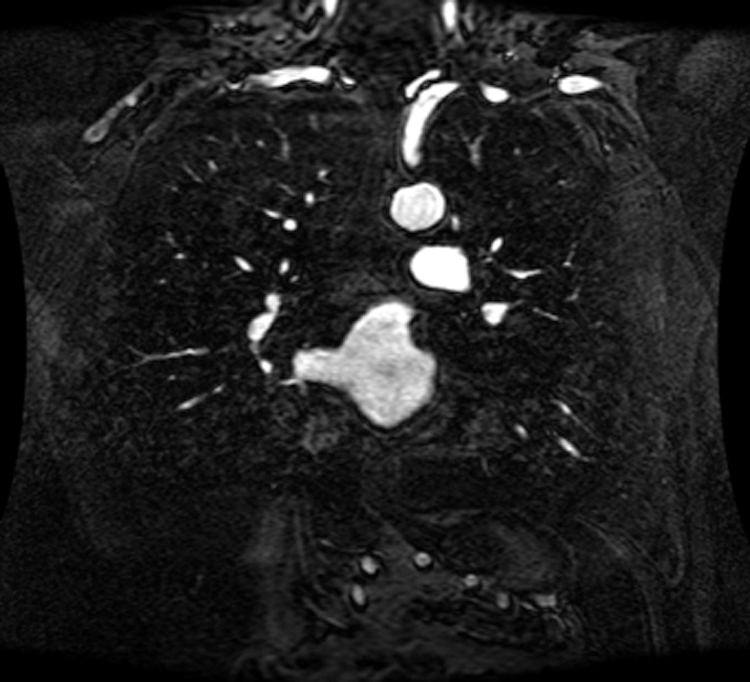

An intelligent-MRI VLC has been implemented for MRI image transmission using VLC and RF interference is eliminated. The proposed intelligent-MRI VLC system is experimentally analyzed using MRI images of different sizes i.e., 100, 115, and 120 KB respectively. These MRI images of the chest are downloaded from a medical database physionet.org. The downloaded MRI images are of T1 weighted type, which has grey matter darker than white matter was used for the proposed work. Images are acquired using Image Acquisition (IMAQ) in LabVIEW and transmitted using visible light in an indoor environment. The downloaded MRI images of various sizes are shown in Figs. 13–15.

Figure 13: 100 KB MRI image

Figure 14: 115 KB MRI image

Figure 15: 120 KB MRI image